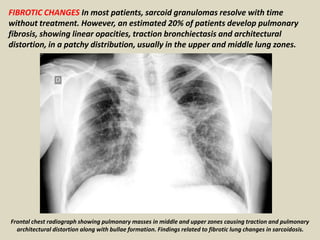

FIBROTIC CHANGES In most patients, sarcoid granulomas resolve with time

without treatment. However, an estimated 20% of patients develop pulmonary

fibrosis, showing linear opacities, traction bronchiectasis and architectural

distortion, in a patchy distribution, usually in the upper and middle lung zones.

Frontal chest radiograph showing pulmonary masses in middle and upper zones causing traction and pulmonary

architectural distortion along with bullae formation. Findings related to fibrotic lung changes in sarcoidosis.